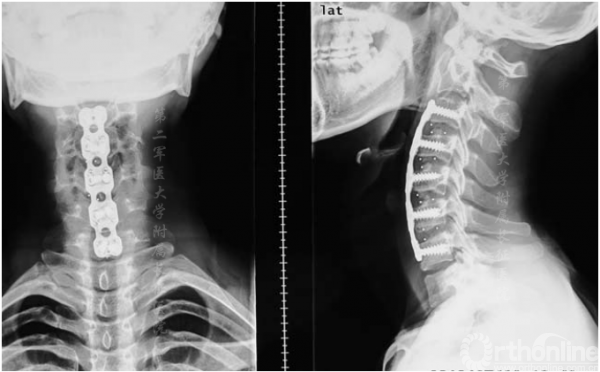

图3.术后x线片显示颈椎前路椎间盘切除术及融合内固定术

颈椎中立位MRI可见颈椎后凸在C4-C5或C5-C6处具有顶点(图1),且脊髓出现轻度萎缩。屈颈位MRI可见硬膜外高信号影及硬膜囊后壁前移(图2)。头颅MRI未显示异常。根据MRI将患者诊断为平山病伴颈椎后凸畸形。入院三天后,患者在全麻下接受颈前路椎间盘切除术并在C3-C7水平融合以重建颈椎序列和脊柱前凸(图3)。

表3列出了有关手术方式、术后情况和随访结果的详细信息。手术时间为2.2到3.4小时(平均2.8小时),失血量为200至460mL(平均300mL);术后第二天在床上开始进行肢体功能锻炼。术后2-3天拔除引流管,并进行X线摄片。术后第五天,患者在无支具辅助下进行下肢锻炼,术后7-10天出院。术后三个月佩戴颈托固定。